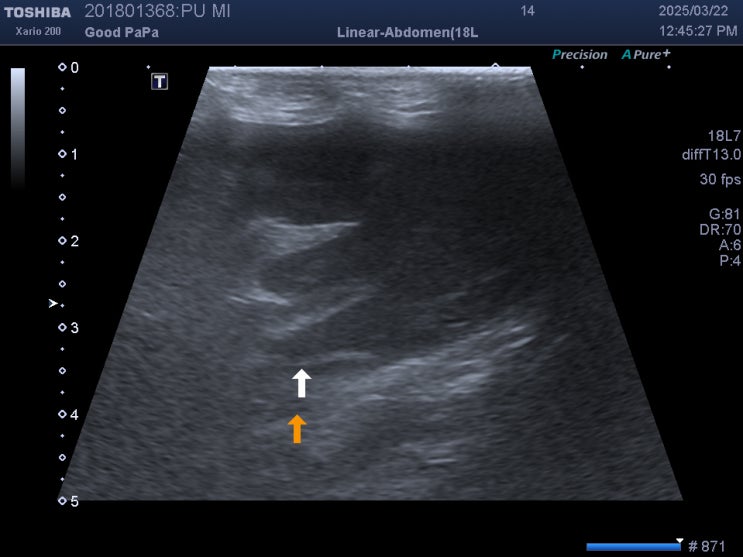

강아지 심장약을 평생 먹어야 하는 이유 / 반려견 폐수종 증상, 치료 후기 / 애완견 기침하면 동물병원에 가야 하는 이유 / 강아지 심장약 복용 간격, 시간

안녕하세요~ 굿파파 수의사입니다. 서울은 벚꽃이 만개하였네요~ 운전하면서 벚꽃 구경하고 하루를 시작합...